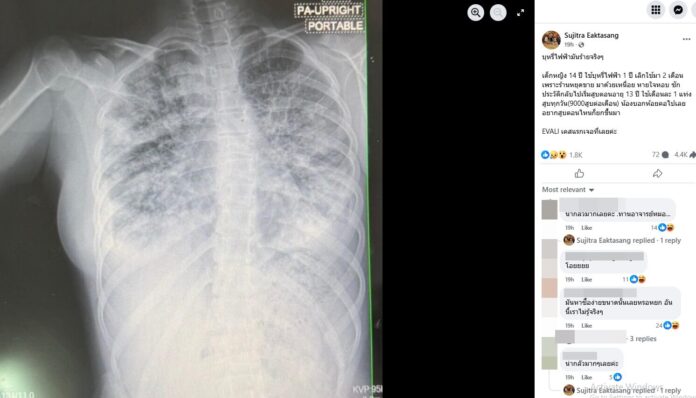

หมอเผยเคสน่ากลัว ด.ญ.วัย 14 ปี สูบบุหรี่ไฟฟ้า 1 ปี ใช้แบบห้อยคอเดือนละแท่ง อยากสูบตอนไหนก็ทำได้เลย ก่อนมาโรงพยาบาลด้วยอาการเหนื่อยหอบ พบเป็นโรค EVALI

วันที่ 22 เม.ย.2568 พญ.สุจิตรา เอกตาแสง โพสต์ข้อความผ่านทางเฟซบุ๊ก Sujitra Eaktasangหลังพบเคสผู้ป่วยเด็กที่สูบบุหรี่ไฟฟ้า ความว่า บุหรี่ไฟฟ้ามันร้ายจริงๆ เด็กหญิง 14 ปี ใช้บุหรี่ไฟฟ้า 1 ปี เลิกใช้มา 2 เดือน เพราะร้านหยุดขาย

มาด้วยอาการเหนื่อย หายใจหอบ ซักประวัติกลับไปทราบว่า เริ่มสูบตอนอายุ 13 ปี ใช้เดือนละ 1 แท่งสูบทุกวัน (9,000สูบต่อเดือน) น้องบอกห้อยคอไปเลยอยากสูบตอนไหนก็ยกขึ้นมา

ผู้ที่ป่วยเป็นโรค EVALI โดยส่วนใหญ่ 95% ผู้ป่วยจะมีอาการ ไข้หนาวสั่น ไอ หายใจลำบาก ปวดเมื่อยตามตัว คล้ายการติดเชื้อไวรัสหรือแบคทีเรีย แต่พบว่า 77% ของผู้ป่วยมีอาการเกี่ยวกับระบบทางเดินอาหาร เช่น คลื่นไส้ อาเจียน ท้องเสีย ซึ่งผู้ป่วยทุกคนมีภาพ X-ray และ CT Scan ปอดมักจะมีความผิดปกติ เป็นฝ้าขาว และจะหายใจไม่ไหว